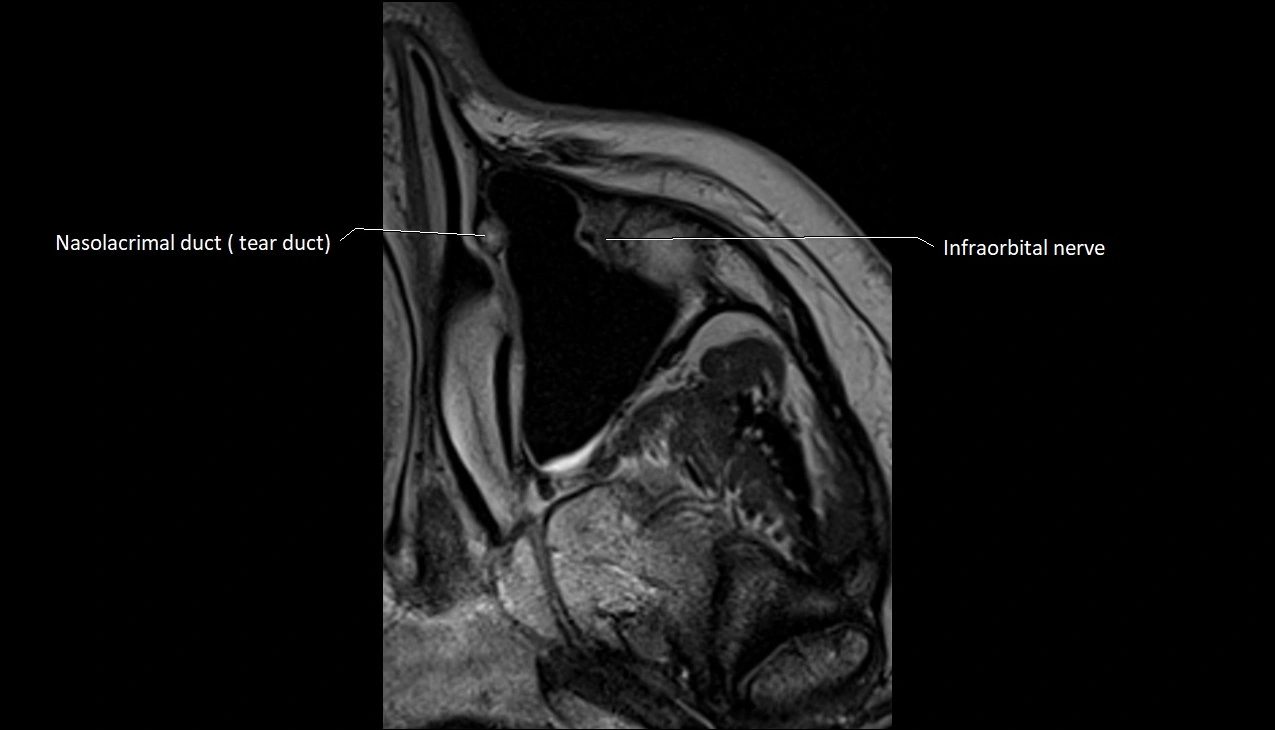

- Nasolacrimal duct (Tear duct)

- Infraorbital nerve